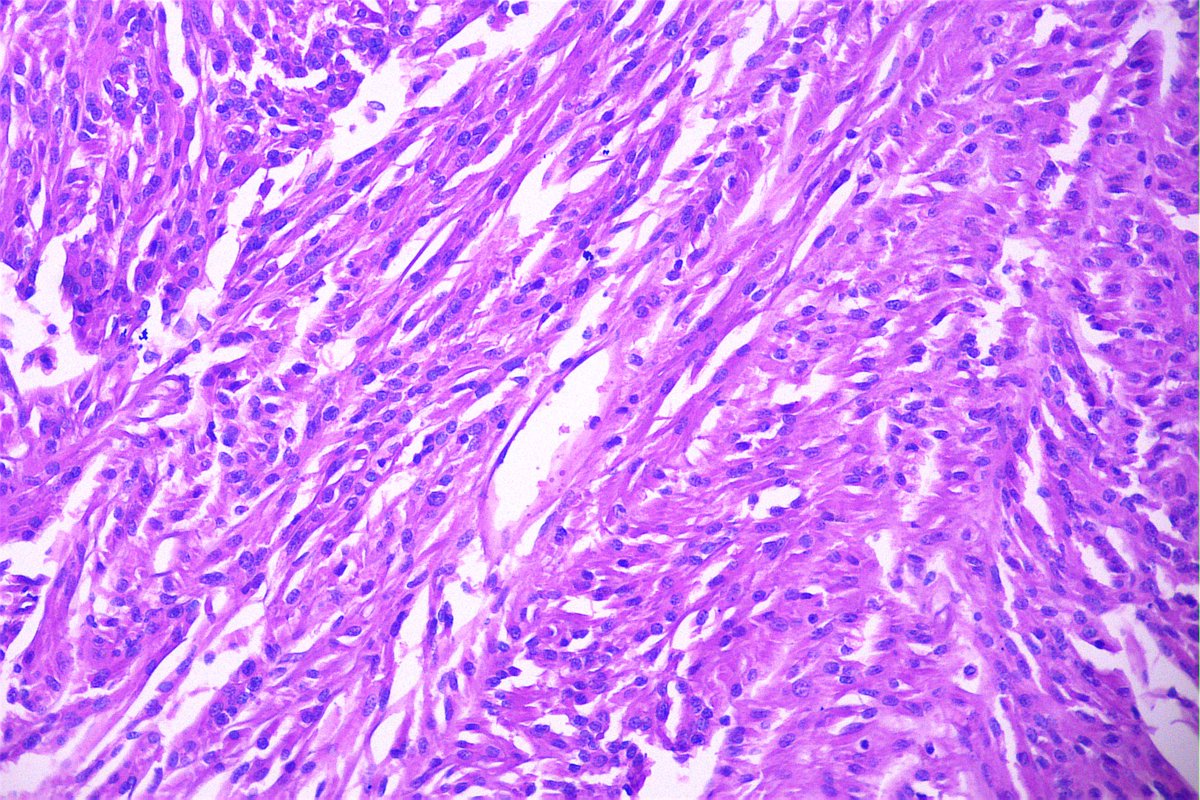

@GeronimoJrLapac

Ger么nimo Jr.

2 months

F, 47yo. The clinical information is: subepithelial lesion in the ileocecal valve. #gipath